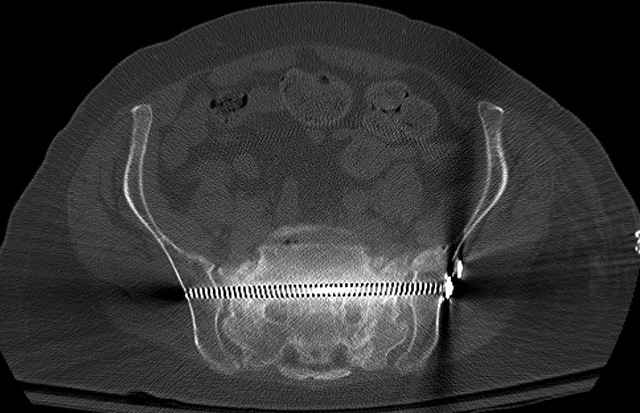

3 Months After Fall

Continued Pain & Immobility

(+) Instability to Compressive Manual Exam

Pelvic CT Scan - 3 Months After Fall

Sacral Injuries

Ramus Fractures